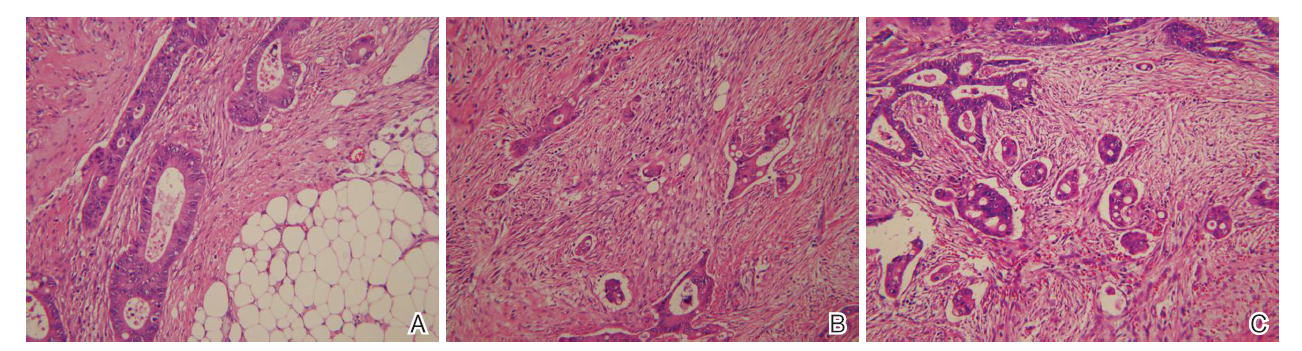

PDC分级与肿瘤浸润深度(T)、淋巴结转移(N)、远处转移(M)、淋巴管血管侵犯(LVI)、外周神经侵犯(PNI)及肿瘤出芽(TB)分级显著相关(P<0.05), 而与性别、年龄、发病部位及肿瘤平均最大径无关(P> 0.05, 表1)。不同分级的PDC特征见图1。

所有肿瘤样本制成苏木精-伊红(hematoxylin and eosin, H-E)染色切片, 由两名病理科医师分别进行独立判读、复核, 并根据第8版美国癌症联合会(American Joint Committee on Cancer, AJCC)癌症手册[7]对肿瘤进行分期。对于每个病例, 根据2019版世界卫生组织(World Health Organization, WHO)标准[8], TDG以腺体比例, 分成TDG-H(腺体比例少于50%)和TDG-L(腺体比例不少于50%)两类; 同时, 根据Ueno等[3, 4, 5]既往描述的PDC标准计数方法, 对肿瘤进行组织学分级。PDC定义为出现在癌巢中的, 由≥5个癌细胞组成的, 但缺乏腺样结构的肿瘤细胞簇(无论簇的大小)。具体操作为:首先使用低倍显微镜扫描全部切片, 在肿瘤浸润前沿找出热点区域, 然后使用20倍物镜对热点区进行计数, 根据PDC的数量分为PDC1(<5群)、PDC2(5~9群)和PDC3(> 10群)3个等级。统计PDC分级在肿瘤浸润深度、淋巴结转移、远处转移、淋巴管血管侵犯、外周神经侵犯、肿瘤出芽以及组织学分化程度各分组中的分布差异。此外, 对Ueno标准进行改良, 将PDC1和PDC2合并定义成低级别PDC(PDC low, PDC-L), 将PDC-3定义为高级别PDC(PDC high, PDC-H), 使用改良PDC系统, 对构成比明显偏大的TDG-L进行再次分层, 比较PDC二分类系统在TDG-L组中肿瘤浸润深度、淋巴管血管侵犯、淋巴结转移、神经侵犯、肿瘤出芽各细化分组中的分布差异。

新近, Ueno等[11]提出了一种基于PDC数量的新分级系统, 并证明了该分级系统在观察者间一致性和预后能力方面的优越性。这个新分级系统, 首先是要对PDC作出定义:在HE切片中, 出现在癌巢中的(往往是浸润前沿), 由≥5个癌细胞组成的, 但缺乏腺样结构的肿瘤细胞簇。如将PDC的数量分为三个等级, 本研究的数据显示:PDC1级肿瘤占27.4%、PDC2级肿瘤占28.3%、PDC3级肿瘤占44.3%。如参照TDG系统, 对应地将PDC也由三分类合并为二分类, 分成高级别(PDC-H, 对应PDC3)和低级别(PDC-L对应PDC1+PDC2), 高级别的比例增加到44.3%, 低级别的比例下降到55.7%, 较传统组织学分级系统, 新的分级系统在每个类别的分布更为平均, 构成比更为合理。